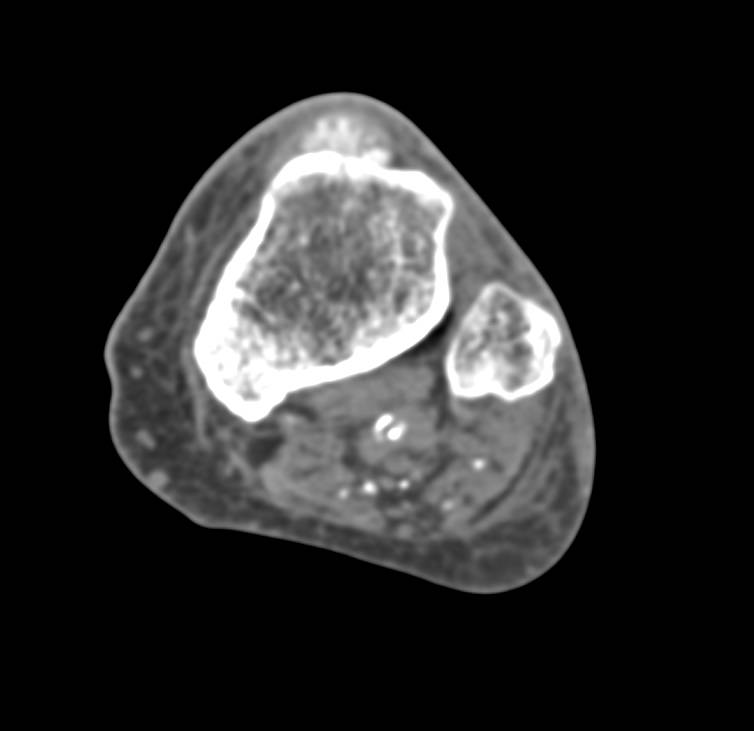

Hemangioma in the Left Paraspinal Muscles